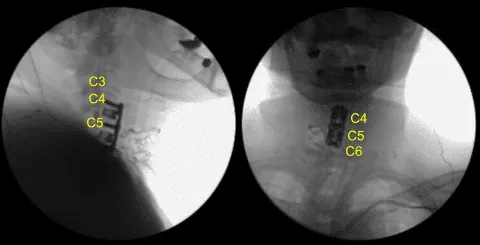

Se utilizaron ensayos para seleccionar un espaciador intersomal lordótico de titanio de 7 mm que se llenó con autoinjerto y aloinjerto fragmentados y se tapeó suavemente en los espacios interseccionales C4-5 y C5-6 con un mazo en la posición correcta. Se retiraron los alfileres de caspar. El defecto óseo fue encerado.

La AP y la fluoroscopia lateral mostraron una posición correcta. Los potenciales evocados motores mostraron una ligera disminución de amplitud en el C5-6 derecho. Posteriormente, la instrumentación fue retirada. El espacio de instrumentación fue limpiado y irrigado con el lavado de la cisterna.

No hubo cambios significativos, por lo que se sustituyó el separador intercarrocado. Los osteófitos anteriores fueron enjuagados con un taladro eléctrico de alta velocidad. La hemostasia se obtenía con cera ósea. Se colocaba una placa lordótica de titanio de C4 a C6 y se aseguraba con un pasador.

La fluoroscopia mostró el tamaño y posicionamiento correctos, por lo que se aseguró con seis tornillos de titanio de 14 mm decorativos con un taladro eléctrico de mano de 12 mm. La apto y la fluoroscopia lateral mostraron buen posicionamiento. Todos los tornillos se apretaban finalmente usando un dispositivo integrado en la placa.